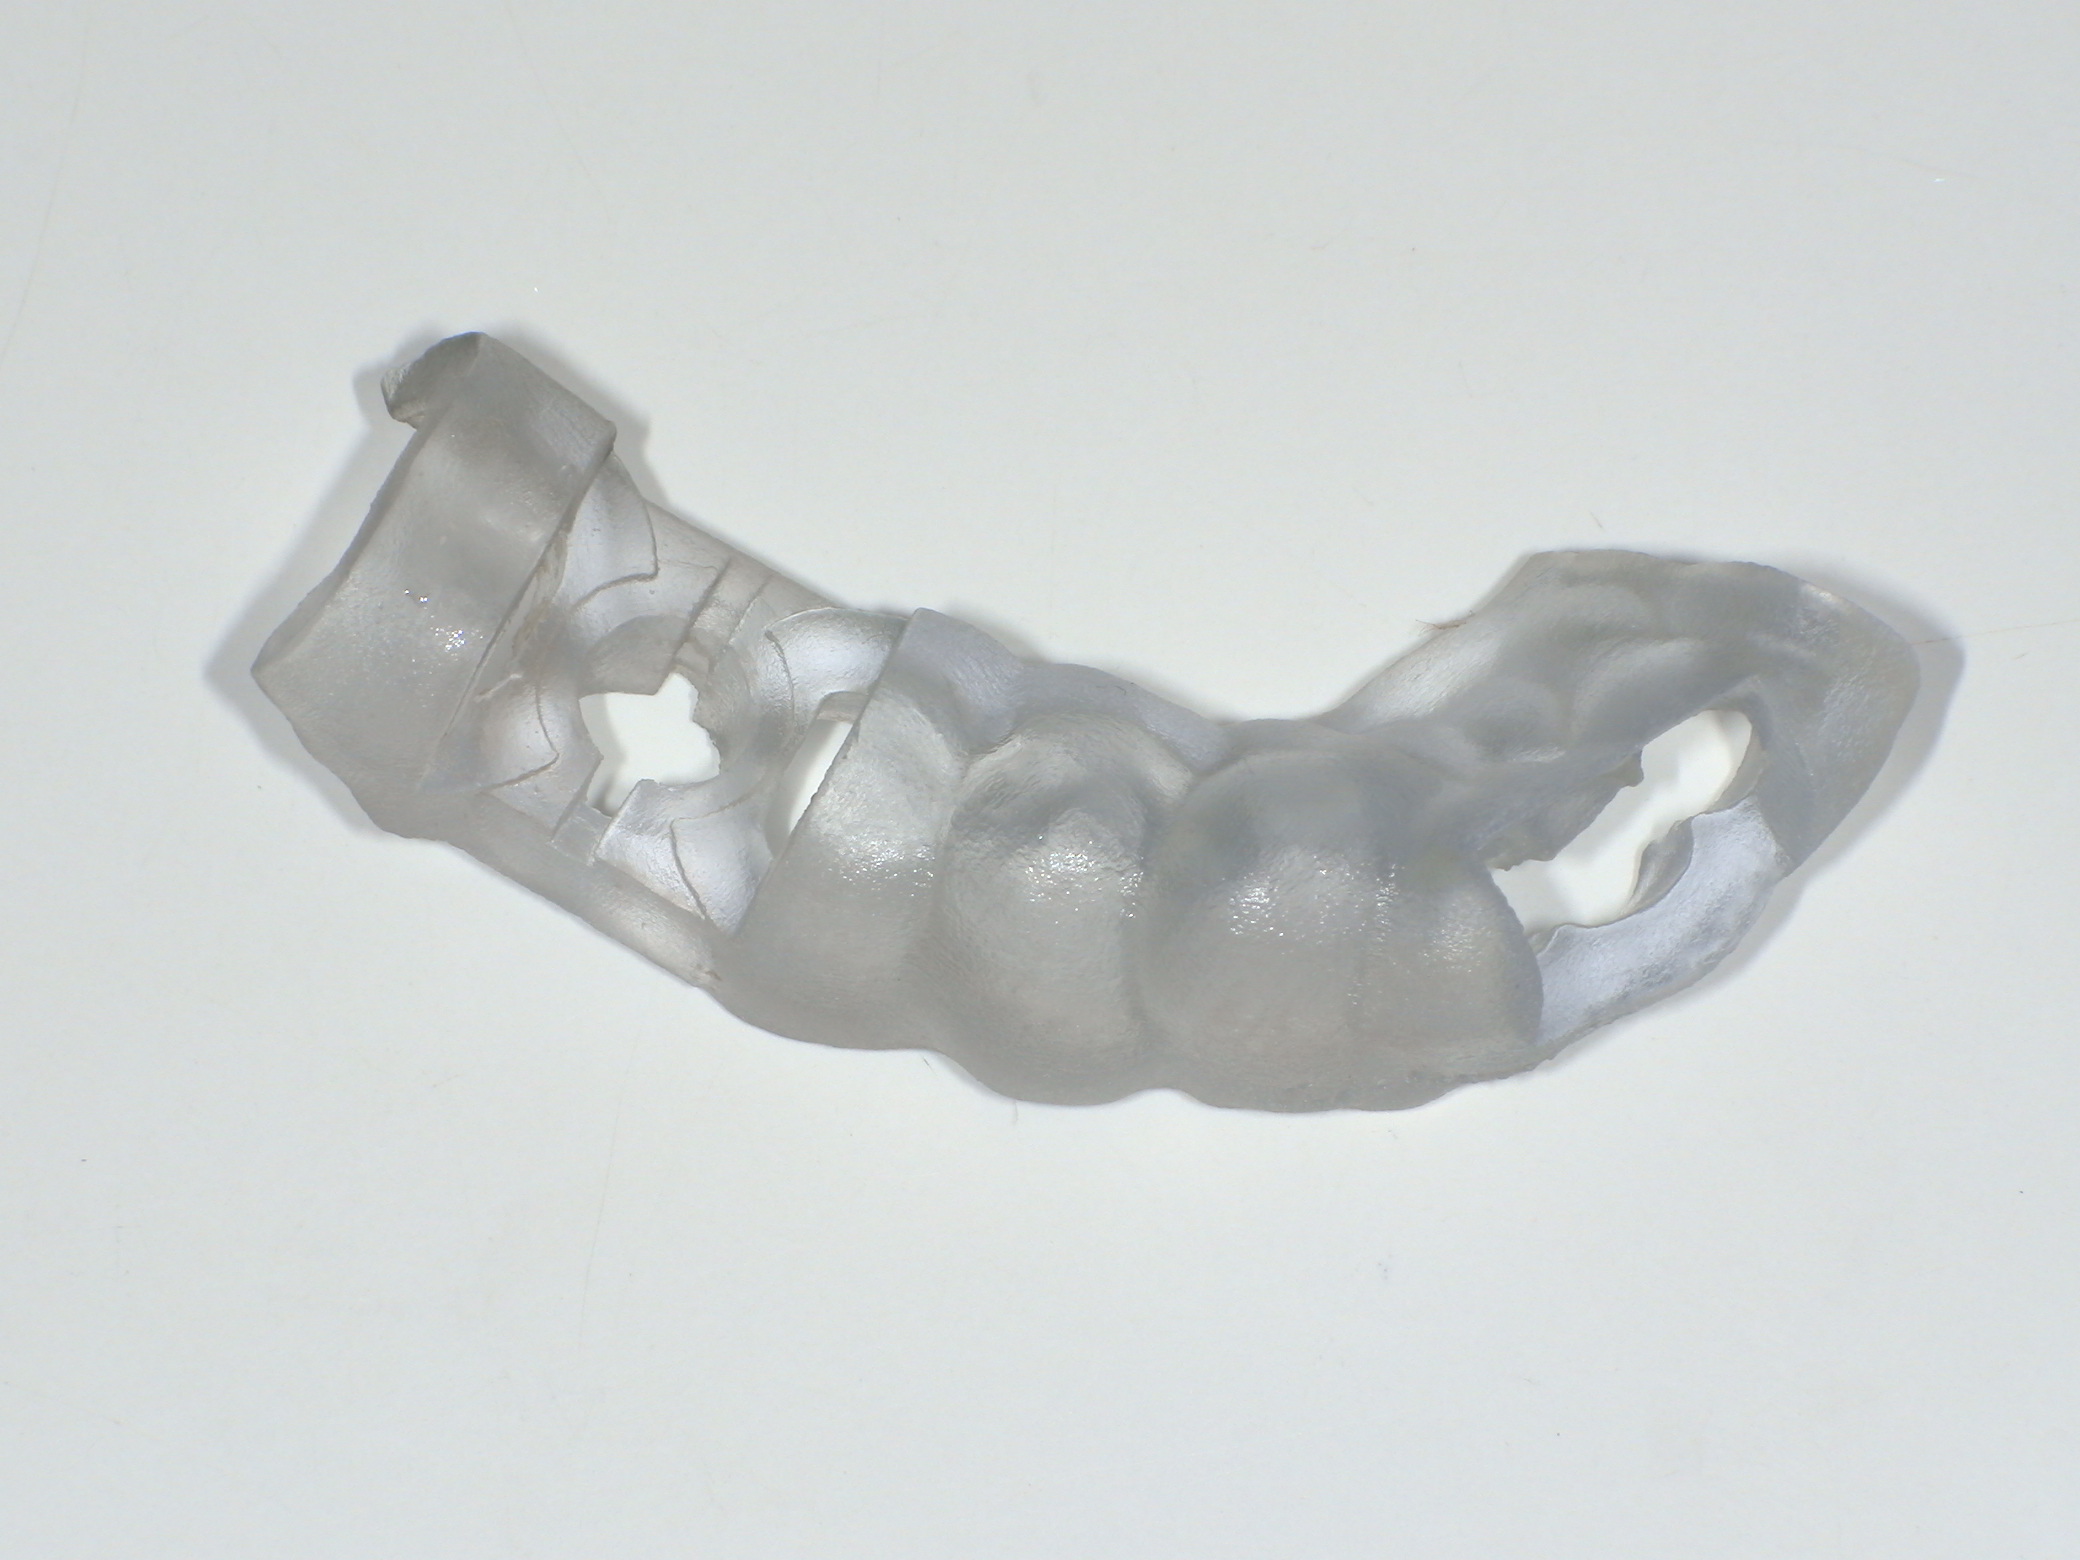

サージカルガイド

インプラントをシミュレーション通りの位置に埋め込むために使用します。サージカルガイドを使用することで、想定している被せ物とインプラントの埋入場所をベストな位置関係にすることが可能となります。